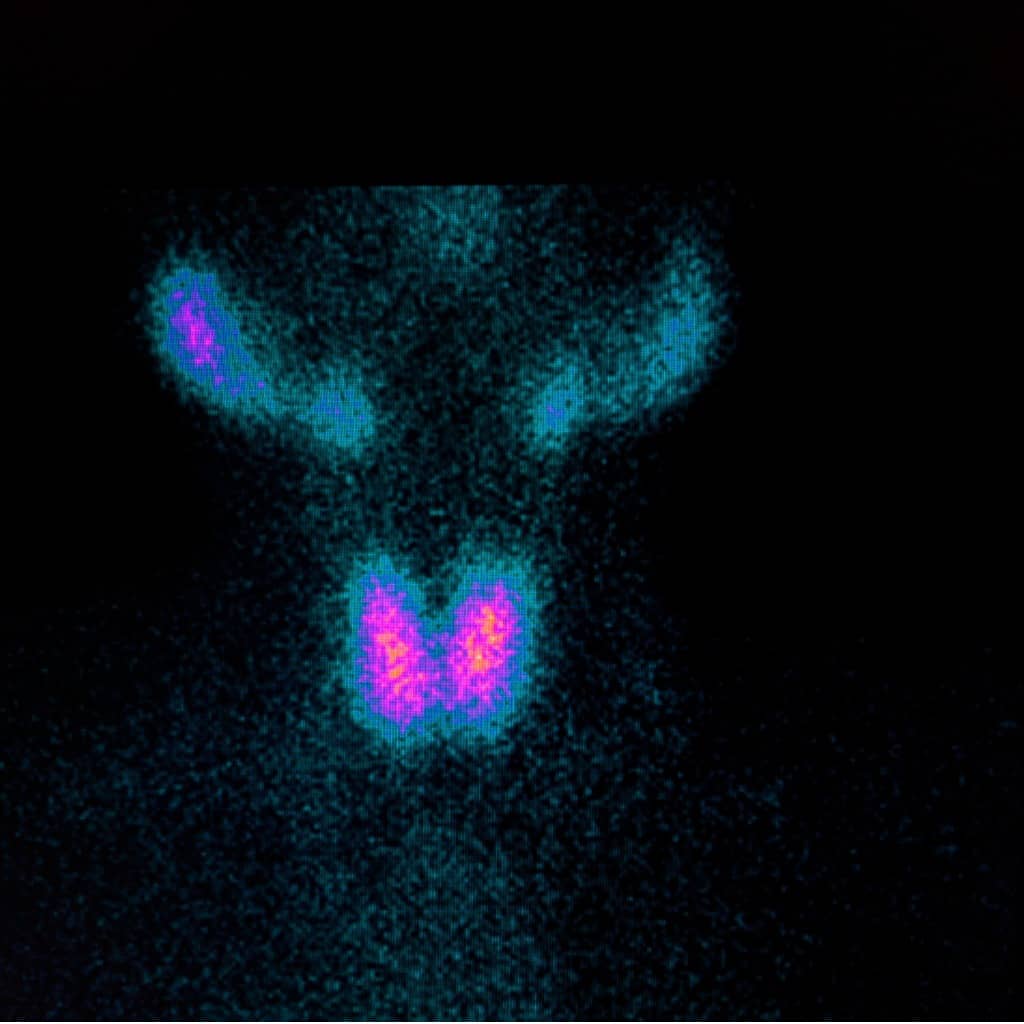

Das Team der Ambulanz führt eine genaue Diagnostik durch, die unter anderem Ultraschalluntersuchungen, Szintigrafien und Blutuntersuchungen umfassen kann. Basierend auf den Ergebnissen erstellen die Fachärzte einen individuellen Behandlungsplan für jeden Patienten, der sowohl konservative als auch interventionelle Therapiemöglichkeiten umfassen kann.

Bei einer nuklearmedizinischen Untersuchung der Schilddrüse werden verschiedene Verfahren angewendet, um die Funktion und Struktur der Schilddrüse zu beurteilen. Dazu gehören unter anderem Szintigrafien, bei denen eine schwach radioaktive Substanz injiziert wird, um die Aktivität der Schilddrüse sichtbar zu machen. Zusätzlich können Ultraschalluntersuchungen durchgeführt werden, um die Größe und Struktur der Schilddrüse sowie eventuelle Knoten oder Veränderungen zu untersuchen. Blutuntersuchungen können ebenfalls Teil der Diagnostik sein, um bestimmte Hormonwerte zu überprüfen. Basierend auf den Ergebnissen dieser Untersuchungen kann das Fachärzteteam der AKH Nuklearmedizin Schilddrüsenambulanz einen individuellen Behandlungsplan für den Patienten erstellen.

In der Radiologie wird die Schilddrüse häufig mittels verschiedener bildgebender Verfahren untersucht. Zu den gängigen Methoden zählen die Ultraschalluntersuchung, die Szintigrafie und die Computertomographie (CT). Bei der Ultraschalluntersuchung kann der Arzt die Struktur und Größe der Schilddrüse sowie eventuelle Knoten oder Veränderungen im Gewebe sichtbar machen. Die Szintigrafie ermöglicht es, die Funktion der Schilddrüse zu beurteilen, indem ein radioaktives Tracer-Mittel injiziert wird, das von der Schilddrüse aufgenommen wird. Die CT-Untersuchung bietet detaillierte Querschnittsbilder der Schilddrüse und umliegender Strukturen. Durch diese radiologischen Verfahren kann eine präzise Diagnose gestellt werden, um eine gezielte Behandlung einzuleiten.